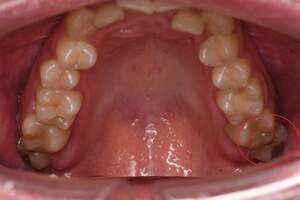

左下の歯茎が腫れている親知らずの症例

左下の親知らず周囲歯肉が腫れていました。

また、手前の歯との間で虫歯もできていました。

口腔内

半埋伏の親知らずでした。3糸縫合しました。